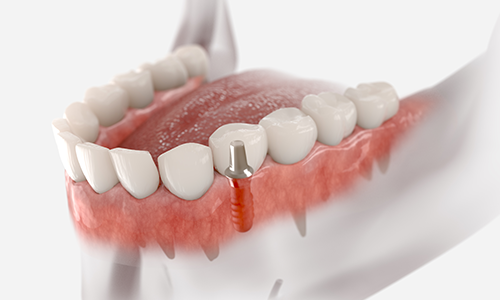

고난이도 임플란트

웃는얼굴치과는 풍부한 경험과 전문성을 바탕으로

일반적인 케이스는 물론,

고난이도의 임플란트 수술까지

안전하게 진행합니다.

뼈 이식이나 발치 즉시 식립 등 까다로운 조건에서도 정밀 진단과

체계적인 시술 시스템으로 환자 맞춤형 치료를 제공합니다.